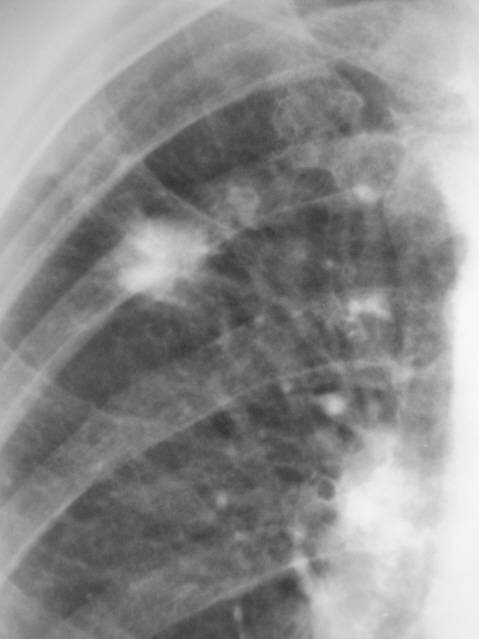

Произведены томограммы.

Какие будут мнения?

Конгломерат извести. При отсутсвии клиниколабораторных данных за активность туб. процесса я бы рискнул оставить пациента в покое на 3 месяца с последующим рентгенологическим контролем.

Я согласен с Вами коллега, мы так и поступили - "оставили его в покое", с последующи контролем через 6 месяцев.

Валентини Львович, в целом впечатление о туберкулёме в стадиии обострения ( инфильтрации?).Рекомендовал бы консультацию в Противотуберкулёзном диспансере!